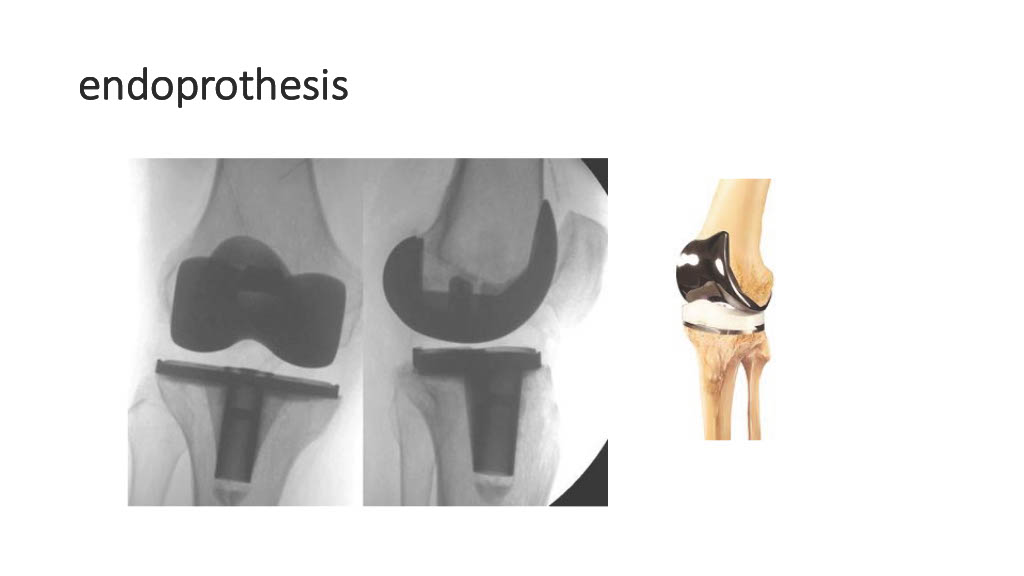

Vogrin, Matjaž, MD, PhD.

Department of Orthopaedics & Sports Medicine Institute, University Medical Centre Maribor, Slovenia

“Surgical treatment of knee injuries in skiing”

Prof. Matjaž Vogrin is an orthopaedic surgeon and specialist in arthroscopic surgery and sports injuries. He is chairman of the Institute of Sports Medicine ” at the Faculty of Medicine in Maribor, Slovenia, and head of the medical subdivision of the Slovenian National Olympic Committee.

He was chief physician of the Slovenian Olympic team at the 2012, 2016, 2021 and 2024 Olympic Games (London, Rio, Tokyo, Paris), official physician of the Slovenian national football team and head of the Slovenian medical team at the 2010 FIFA World Cup in South Africa. He has also been head of the medical team of FC Maribor ( UEFA Champions League and Europa League participants) since 1999. He has been an invited speaker at sports medicine congresses and conferences worldwide.

Surgical treatment of knee injuries in skiing